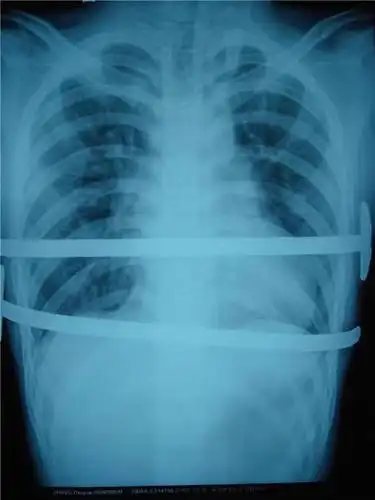

鸡胸图片什么样子鸡胸的危害和造成的鸡胸原因

鸡胸最开始只会出现轻微的骨骼凸起到严重的鸡胸胸骨两侧会向内凹陷